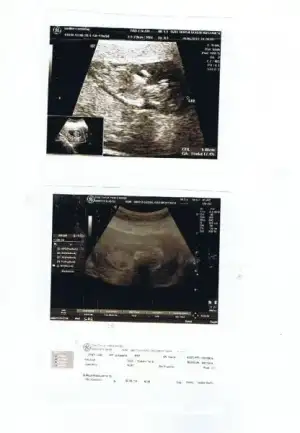

iki oğlum var 14 haftalık hamişim.ilk resim 11+5, ikinci resim 13+5 yorumlayabilirmisiniz.arkadaşlar ve orkdm yorum bekliyorum.çok merak ediyorum.:2:

Eklentiler

• $Resim4.webp

$Resim4.webp

14,5 KB · Görüntüleme: 89

Ben yanlışlıkla iki kere yüklemiştim arkadaşlar :) heyecandan ... İlk foto 12+5 2. 11+5 3. De 11+5 diğerleri de aynı zaten